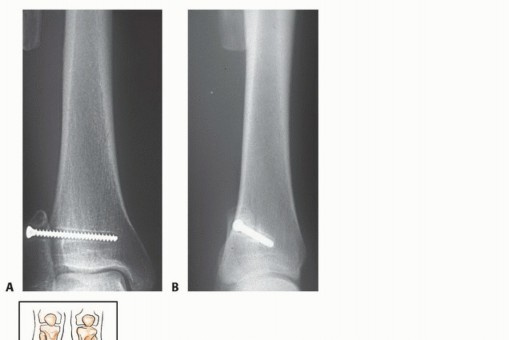

الأشعة السينية (X-rays): هي الخطوة الأولى غالبًا. توفر صورًا للعظم وتكشف عن التغيرات في بنية العظم، مثل التآكل، التصلب، أو وجود كتلة. يمكن أن تعطي مؤشرات أولية حول طبيعة الورم (حميد أو خبيث).

-